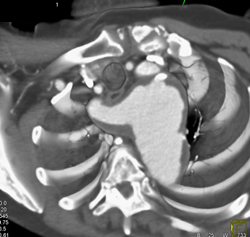

Right Coronary Aneurysm